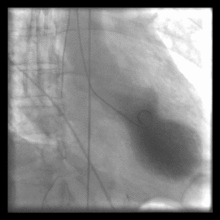

Cardiac ventriculography

Cardiac Ventriculography is a medical imaging test used to determine a patient's cardiac function in the right, or more typically, left ventricle. Cardiac ventriculography involves injecting contrast media into the heart's ventricle(s) to measure the volume of blood pumped. Cardiac ventriculography can be performed with a radionuclide in radionuclide ventriculography or with an iodine-based contrast in cardiac chamber catheterization.